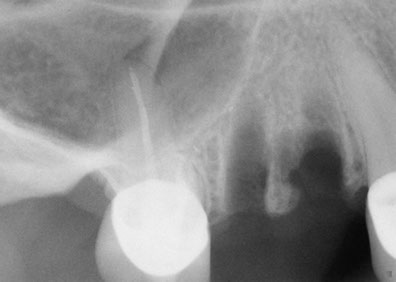

A quick and safe solution to facilitate the installation of dental implantsIn 1960, it was Philip Boyne who first used the Caldwell-Luc procedure to correct the lack of maxillomandibular space by raising the sinus membrane in the area of the molars and premolars and placing a graft composed of particulate or autogenous corticocancellous bone (originating from the patient) at the base of the to fill the bone cavity. With the arrival of titanium root implants, it was discovered that many people’s upper maxillary bones were inadequate in height and bone width, requiring a bone graft in the maxillary sinus to make them suitable recipients of for dental implants. A sinus lift is a surgical procedure that is necessary when there is insufficient bone, during which bone is added in between the upper maxilla and the maxillary sinuses, which are an annex to the nasal passages. Found on both sides of the nose, the shape and size the maxillary sinus varies in each person and with the passage of time it becomes larger (inappropriate for dental implants).

Who is a candidate for this technique?This technique is recommended in cases where it is impossible to place dental implants with the proper length required in the posterior upper jaw bone. In this area there is usually a type III or IV bone quality and because of this, it is necessary to use an implant with a minimum length of 10mm and the largest possible diameter.